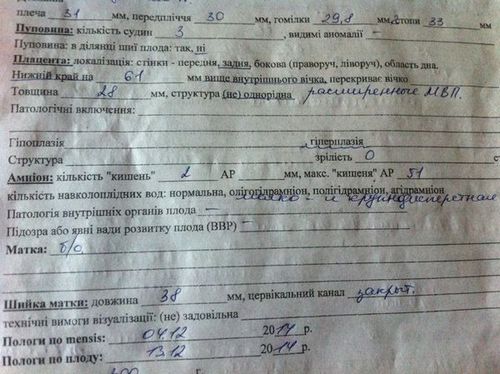

Параметри узі 20 тижні

При двадцатінедельном УЗД неодмінно проводять фетометрію дитинку, тобто уточнюють його розміри. Зазвичай дослідження проводять за чотирма тенденціям. Всі параметри вказують в результатах обстеження. Також визначається і вага малюка. При нормі в 400г, його зріст приблизно 19-21см.

Визначає УЗД і в якому стані перебуває плацента. Особливо важливо це дослідження, якщо по якомусь показнику плід відстає в розвитку. Закінчується УЗД оглядом нирок самої матусі. Адже крім здоров'я самого малюка лікар повинен упевнитися в здоров'я самої жінки.

Здрастуйте, 30 років 20 і 4 неделя.Второе УЗД сьогодні було, порекомендували консультацію у генетика бо побачили гіперплазію плаценти і доліхоцефаліческая форму голови.Скажіте, навіщо потрібен генетик і які ще додаткові обстеження потрібні? Перший скринінг показав відмінні результати-я з вами тут вже радилася :) Спасибо :)

Плацента в 28 мм є нормальною, а ось форма голови - немає, і може битьіз наявність хромосомного або генетичного дефекту. Вам потрібна консультація НЕ генетика (він нічого толком не скаже), а повторне УЗД в перинатальному центрі, яку має провести досвідченим професіоналом. Якщо така форма голови підтвердиться, якщо виявляться інші відхилення, вам можуть запропонувати амніоцентез для кариотипирования навколоплідних вод. А вже після цього буде стояти питання, потрібна вам консультація генетика чи ні. Повторю ще раз: проблема не в плаценті, а в голові.

З додаткові інформації є що цефалического індекс 70% - це дає більше інформації на цей період? На Узі мені сказали, що на 20 тижні це може бути і вона ще може змінитися.

Цефалического індекс в нормі 74 - 83. Він додатково ні про що не говорить, крім того, що розміри голови не в нормі. Ситуація оцінюється разом з іншими параметрами УЗД, даними пренатального генетичного скринінгу. Вам потрібно осмореть УЗД-перинатології, який має підготовку в такого роду УЗД.